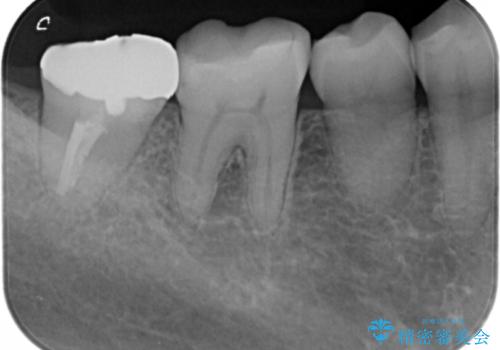

- 右下奥歯(7番)の高さがなく、かぶせ物(クラウン)にするためにあらかじめ歯周外科手術を行いました。(クラウンレングスニング)

特に根尖に症状がなかったため、右下7番の根管治療はやり直していません。

- 56.1万円(右下567 ジルコニアクラウン11万円×3 歯周外科手術APF 15万円 仮歯1万円×3)費用は治療当時の料金となります

歯の高さを出すとかぶせ物(クラウン)がはずれにくくなります。

今回は右下7番が神経のない歯だったため、クラウンにして割れにくくしています。